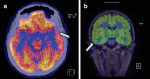

Purpose: Individuals with drug-resistant epilepsy may benefit from epilepsy surgery. In nonlesional cases, where no epileptogenic lesion can be detected on structural magnetic resonance imaging, multimodal neuroimaging studies are required. Breath-hold-triggered BOLD fMRI (bh-fMRI) was developed to measure cerebrovascular reactivity in stroke or angiopathy and highlights regional network dysfunction by visualizing focal impaired flow increase after vasodilatory stimulus. This regional dysfunction may correlate with the epileptogenic zone. In this prospective single-center single-blind pilot study, we aimed to establish the feasibility and safety of bh-fMRI in individuals with drug-resistant non-lesional focal epilepsy undergoing presurgical evaluation.

Methods: In this prospective study, 10 consecutive individuals undergoing presurgical evaluation for drug-resistant focal epilepsy were recruited after case review at a multidisciplinary patient management conference. Electroclinical findings and results of other neuroimaging were used to establish the epileptogenic zone hypothesis. To calculate significant differences in cerebrovascular reactivity in comparison to the normal population, bh-fMRIs of 16 healthy volunteers were analyzed. The relative flow change of each volume of interest (VOI) of the atlas was then calculated compared to the flow change of the whole brain resulting in an atlas of normal cerebral reactivity. Consequently, the mean flow change of every VOI of each patient was tested against the healthy volunteers group. Areas with significant impairment of cerebrovascular reactivity had decreased flow change and were compared to the epileptogenic zone localization hypothesis in a single-blind design.

Results: Acquisition of bh-fMRI was feasible in 9/10 cases, with one patient excluded due to noncompliance with breathing maneuvers. No adverse events were observed, and breath-hold for intermittent hypercapnia was well tolerated. On blinded review, we observed full or partial concordance of the local network dysfunction seen on bh-fMRI with the electroclinical hypothesis in 6/9 cases, including cases with extratemporal lobe epilepsy and those with nonlocalizing 18F-fluorodeoxyglucose positron emission tomography (FDG-PET).